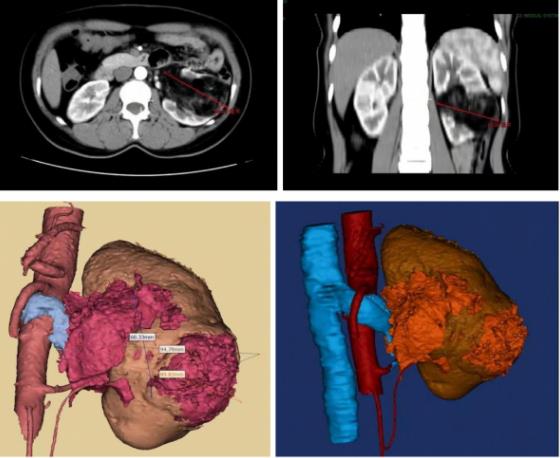

湖醫(yī)附一醫(yī)院3D打印技術(shù)再顯神威幫助泌尿外科成功“拆彈”

近20年來(lái),以泌尿外科為代表的微創(chuàng)外科技術(shù)取得了跨越式發(fā)展,改變了傳統(tǒng)開(kāi)腹手術(shù)創(chuàng)傷大,術(shù)后恢復(fù)慢的劣勢(shì)。而3D打印技術(shù)的應(yīng)用讓“精準(zhǔn)外科”得以看得見(jiàn)、摸得著,進(jìn)一步為患者提供了更為高質(zhì)量的診療服務(wù)。